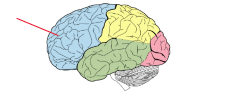

lobus frontalis

lobus parietalis

lobus occipitalis

lobus temporalis

insula

gyrus precentralis

gyrus postcentralis

sulcus centralis

sulcus lateralis